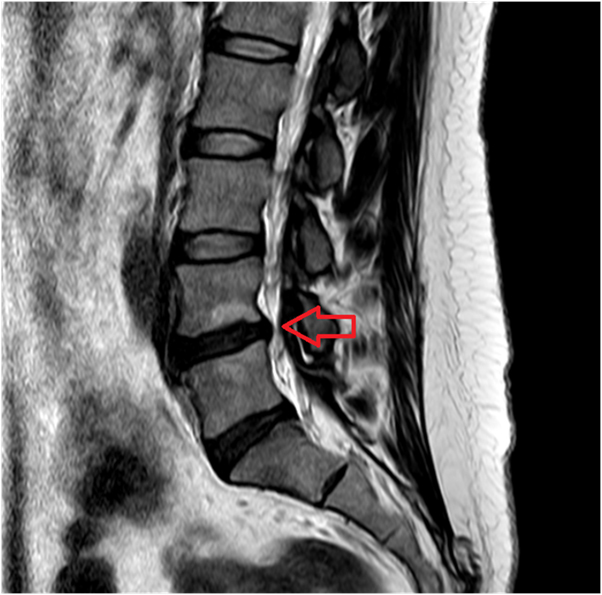

요추 MRI에서 자궁근종 다발 확인(4.3cm, 2.6cm). 정기 추적 계획.

• MRI: 허리디스크 발견 MRI: 허리디스크 발견

• MRI: 자궁근종 발견 MRI: 자궁근종 발견